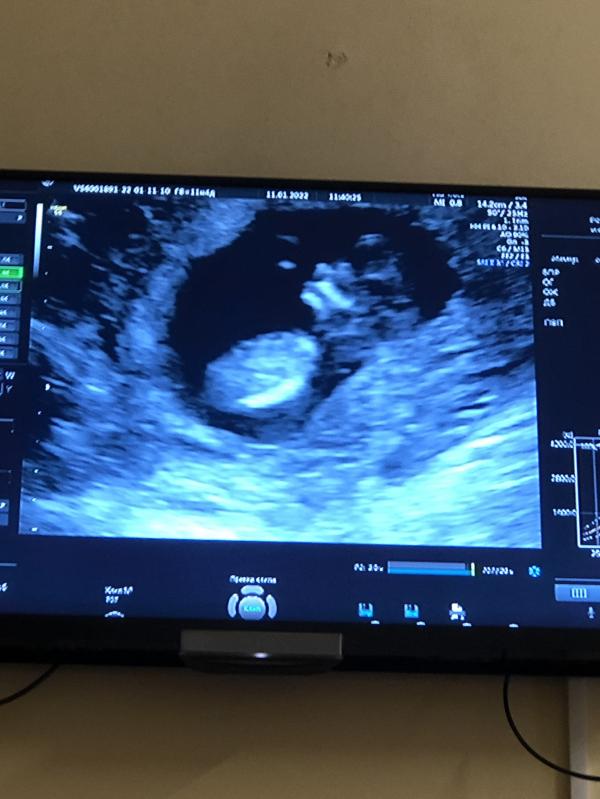

Ну вот и мой первый скрининг. Это было весело😅 Таких подвижных на узи я ещё не видела.Ели поймали для фото. Убегал как мог😅 жалко нельзя видео добавить